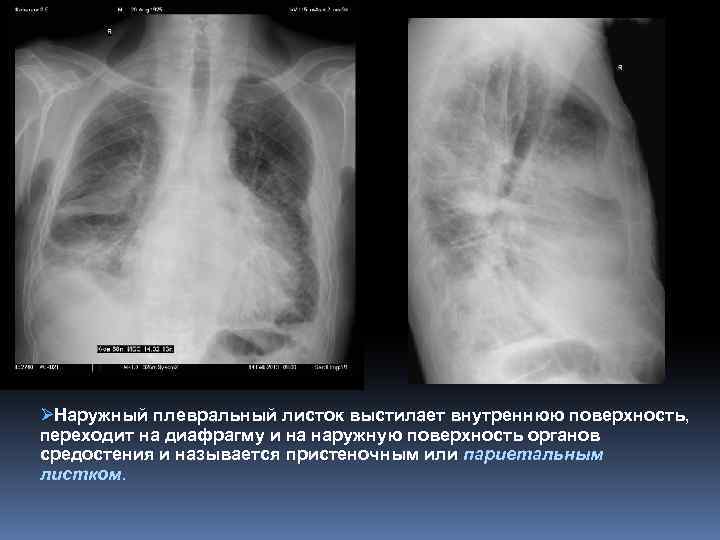

Плевра Ø Плевра – серозная оболочка, покрывающая легкие, внутреннюю поверхность грудной клетки, средостение и диафрагму. Ø Плевра образует замкнутый серозный мешок – плевральную полость. В норме в ней имеется тонкий слой жидкости, обеспечивающий скольжение легких во время дыхательных движений. Ø Выделяют висцеральную (легочную) и париетальную плевру. Ø Внутренний - висцеральный плевральный листок покрывает легкое, срастаясь с его поверхностью, за исключением области корня, где на уровне ворот легкого имеется плевральное окно.

Плевра ØНаружный плевральный листок выстилает внутреннюю поверхность, переходит на диафрагму и на наружную поверхность органов средостения и называется пристеночным или париетальным листком.